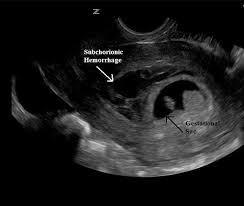

It’s important to understand that fluid in the cul-de-sac during early pregnancy doesn’t automatically mean an ectopic pregnancy. While it can be a sign, other factors need to be considered. For example, hCG levels that aren’t rising as expected and an ultrasound that can’t pinpoint the pregnancy location might point towards an ectopic pregnancy. In such cases, procedures like dilation and curettage (D&C) or manual vacuum aspiration (MVA) might be recommended. These procedures can help determine if a gestational sac or chorionic villi are present, which can offer more definitive information.

While fluid in the cul-de-sac can sometimes be a sign of an ectopic pregnancy, it’s not always the case. The cul-de-sac is a small pouch located behind the uterus. It’s normal to have a small amount of fluid in the cul-de-sac, especially after your period. During early pregnancy, this fluid can sometimes increase due to hormonal changes, blood flow, and the growing uterus.

However, if the amount of cul-de-sac fluid is significant, or if it’s accompanied by other symptoms like pain, bleeding, or fever, it’s important to consult a doctor. These symptoms could indicate a more serious condition, such as an ectopic pregnancy.

It’s crucial to remember that an ectopic pregnancy occurs when a fertilized egg implants outside the uterus, typically in the fallopian tube. This is a serious medical condition that requires immediate attention. If you’re experiencing any of these symptoms, seek medical care immediately.